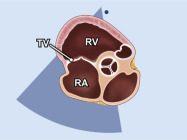

| 2.6. Mặt cắt trục dài cạnh ức qua buồng nhận thất phải |

||||||||

|

|

Cửa sổ siêu âm cạnh ức

Mặt cắt trục dài cạnh ức Ngả đầu dò xuống dưới hướng về phía đùi phải của bệnh nhân |

Nhĩ phải (RA) Van ba lá (TV) Thất phải (RV) |

|||||